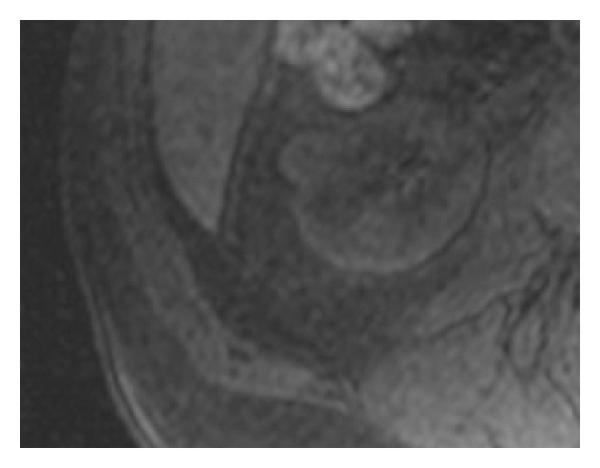

At MR, a pseudocapsule was seen as a hypointense thin rim surrounding the tumor on both T1- and T2-weighted images and is more difficult to detect in hypointense tumors [60, 61]. With postcontrast images, late enhancement of the pseudocapsule resulted in poor contrast relative to the surrounding tissue, lessening its own visualization in this sequence (see Figure 13). Some reports [61, 62] noticed that the presence of a pseudocapsule offers an additional value for local staging. On that series, T2-weighted imaging was the most sensitive technique for visualization of the pseudocapsule (sensitivity: 68%; specificity: 91%), and is corroborated by other authors [15, 63, 64]. For this reasons, MR shows a moderate to high sensitivity in depicting the pseudocapsule than CT [49]. In some large tumors, although tumor invasion was seen, a residual pseudocapsule was found in some areas.

(a)

(b)